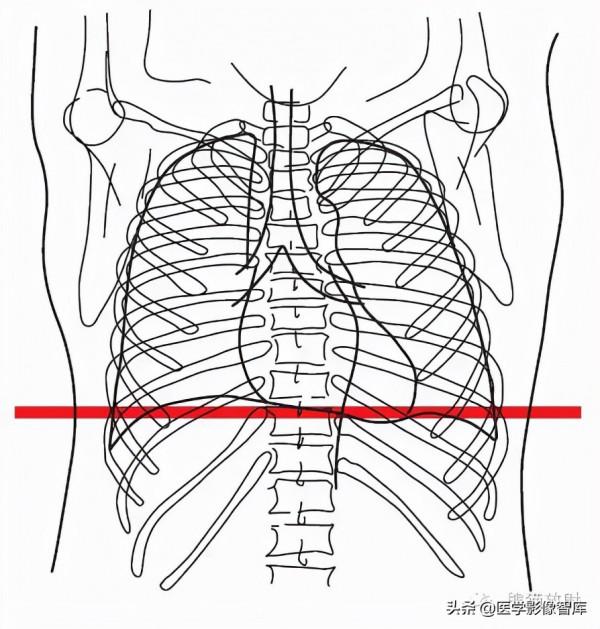

第十層:升主動脈根部水平